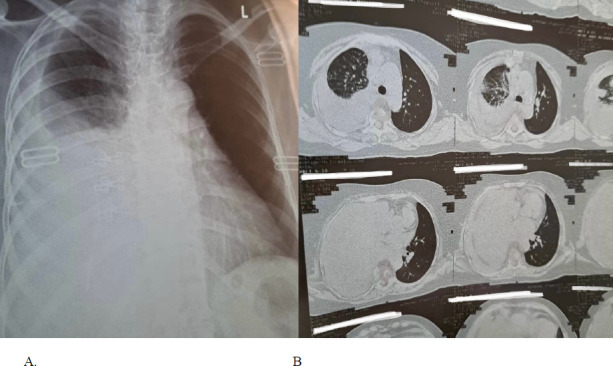

We present the case of a 63-year-old male patient with a history of chronic obstructive pulmonary disease (COPD), heavy smoking, and poor dental hygiene, who presented with progressive dyspnea, fever, and a productive cough. The patient was initially evaluated for pneumonia, but a chest radiograph revealed a right-sided pleural effusion. Further analysis of the pleural fluid showed an exudative effusion. Histopathological examination of a pleural biopsy sample identified gram-positive branching filamentous rods with yellow sulfur granules, consistent with a diagnosis of pulmonary actinomycosis. The patient was initially treated with intravenous amoxicillin/sulbactam, later switched to oral amoxicillin. This case highlights a rare clinical presentation of pleural effusion in a patient with pulmonary actinomycosis.